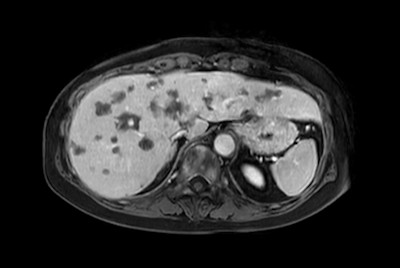

Liver metastasis with SmartSpeed Precise

SmartSpeed Liver

Liver quantification

Fatty liver with MR Elastography

Liver metastasis

Liver metastasis – Free breathing

Liver with MRCP

Liver hemangioma with Compressed SENSE

Liver and Pancreas

Comprehensive Liver exam of focal liver lesions

Liver MR imaging

Comprehensive Liver imaging at 3.0T

Comprehensive Liver imaging at 1.5T